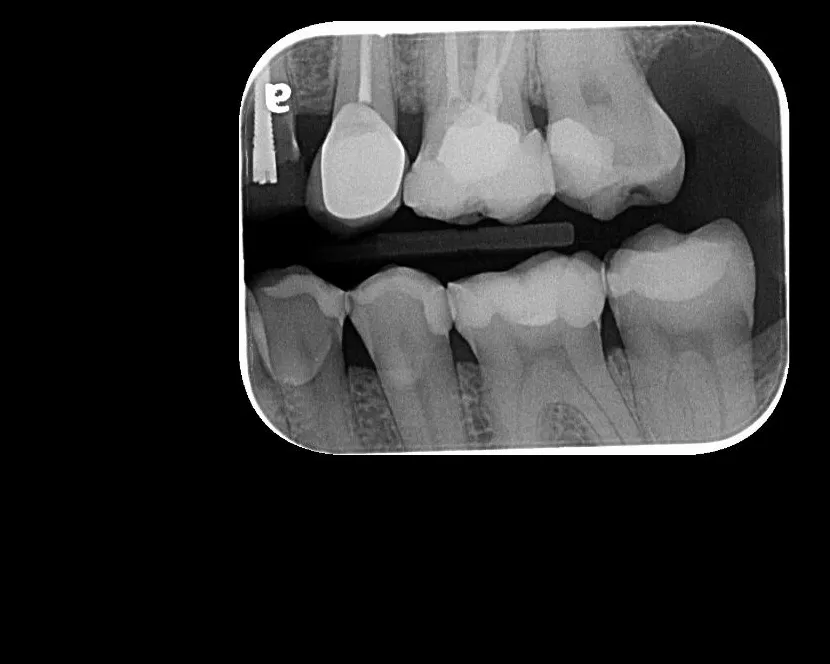

La radiografía intraoral permite observar con gran detalle los dientes y las estructuras que los rodean. Es una herramienta fundamental para detectar caries, infecciones, fracturas, alteraciones en la raíz dental o en el hueso de soporte.

• Ideal para tratamientos de endodoncia, implantología y control preventivo.